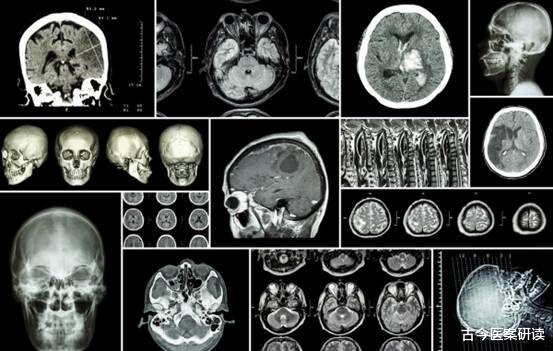

导语:提起高血脂 , 相信大家并不陌生 , 根据相关统计显示 , 目前我国出现血脂异常的人数已经超过了4亿人 , 这是个多么可怕的数字!但是依旧有很多人不重视 , 直到病情恶化 , 出现并发症了才会后悔莫及 。

经过医生检查 , 胡大叔被确诊为急性脑梗 , 不过目前已经脱离了生命危险 。 在与家属的谈话中了解到 。